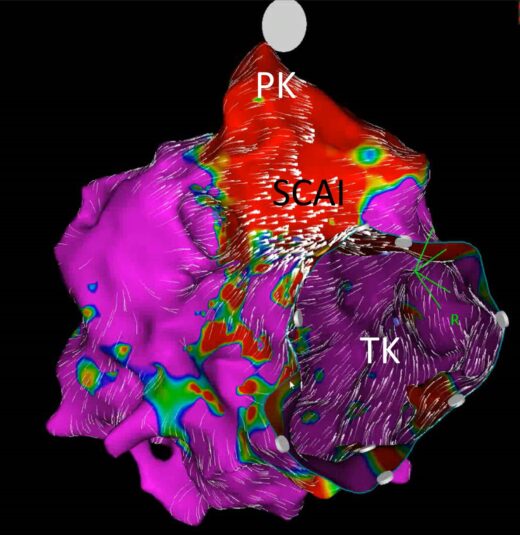

Ein Beispiel ist die Fallot’sche Tetralogie, also ein angeborener Herzfehler, bei dem das Herz und die Gefäße in seiner Nähe nicht richtig ausgebildet sind. Dadurch fließt weniger Blut in die Lunge, was die Sauerstoffversorgung im Körper verringert. Diese wird meist im ersten Lebensjahr operiert. Später können jedoch Herzrhythmusstörungen auftreten, oft aus der rechten Herzkammer. Diese sogenannten Kammertachykardien sind gefährlich und können im schlimmsten Fall zum plötzlichen Herztod führen. Sie entstehen durch Narben und langsam leitende Bereiche im Herzen, sogenannte SCAI (slow conducting anatomic isthmuses).

Die Elektroanatomische Karte zeigt den langsam leitenden Bereich (SCAI) im rechten Herzen zwischen Pulmonal- und Trikuspidalklappe – hohes Risiko für gefährliche Rhythmusstörungen, eine Behandlung ist nötig. Bild: Abteilung für Kinderkardiologie, Herzzentrum Leipzig

Sogenannte SCAI – langsam leitende Zonen im Herzen, die gefährliche Rhythmusstörungen auslösen können – wurden bisher nur durch invasive Katheteruntersuchungen sichtbar gemacht. Dabei hilft ein elektroanatomisches Mapping, das wie eine dreidimensionale Landkarte die Reizleitungsstörungen im Herzen darstellt.